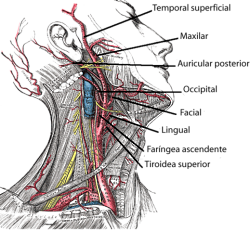

La arteria carótida externa es uno de los vasos sanguíneos más importantes implicados en la irrigación de las estructuras de la cara y el cráneo.

Tiene un recorrido ascendente desde su inicio a nivel de la cuarta vértebra cervical. En su camino da seis ramas colaterales que se encargan del suplemento sanguíneo de las estructuras del cuello y de la cara.

Algunas de sus ramas más importantes son la arteria tiroidea superior y la arteria facial.

La carótida externa completa su recorrido a nivel de la articulación temporo-mandibular y es allí donde se divide dando sus dos ramas terminales, la arteria temporal superficial y la arteria maxilar interna.